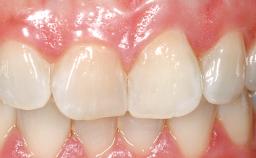

Late Placement of an Implant in a Maxillary Left Central Incisor Site

A 36-year-old female patient was referred for the replacement of the upper left central incisor (tooth 21), which had fractured. Although the tooth had been asymptomatic for many years, the crown began to loosen, at which time she presented to her dentist for an assessment. Teeth 21 and 22 had both been endodontically treated many years previously. She was a healthy individual and a non-smoker.

On examination, the patient had a low lip line and only displayed the coronal half of the anterior teeth when smiling.

The crown of tooth 21 was splinted to the adjacent teeth with composite resin, and the gingiva was inflamed.